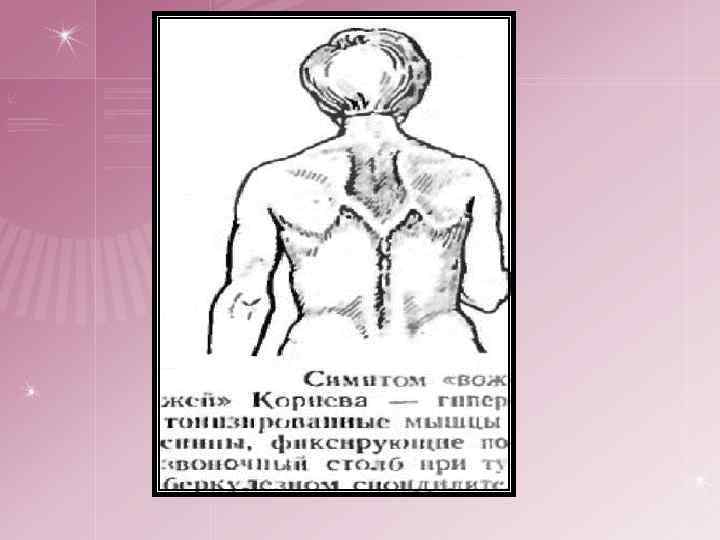

спондилическая артритическая Начальная стадия Общие - соответствует выходу туберкулезного процесса за пределы костного очага, поэтому сопровождается усилением туберкулезной интоксикации Местные: ¤ боли в позвоночнике, схожие с радикулитом, межреберной невралгией ¤ боли могут иррадиировать во внутренние органы ¤ ригидность мышц – ограничение движений в позвоночнике ¤ возникает симптом «вожжей» П. Г. Корнева переход туберкулезного процесса на сустав и развитие туберкулезного синовита. ¤ Постоянные боли, ригидность мышц, сглаженность контуров сустава, ограничение движений, хромота ¤ Слабовыраженные трофические расстройства: гипотония — ослабление тонуса мышц, атрофия мягких тканей, утолщение кожной складки на стороне поражения (симптом Александрова) При переходе туберкулезного процесса на сустав путем прорыва через суставной хрящ наблюдаются выраженные симптомы воспаления: высокая температура тела, быстро развившийся отек, параартикулярных мягких тканей, более редкое ограничение движений, блокада сустава.